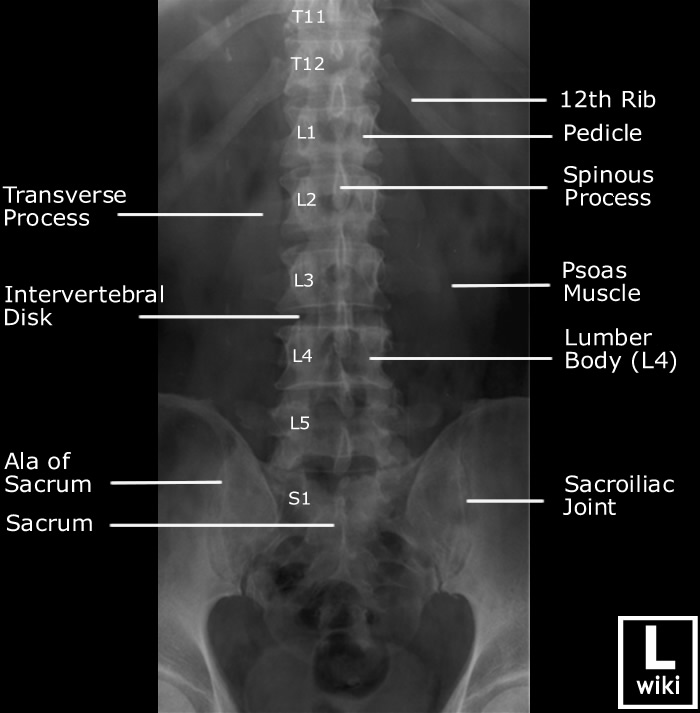

| AP view (Lumbar) | AP view (Sacrum) |

![]() |